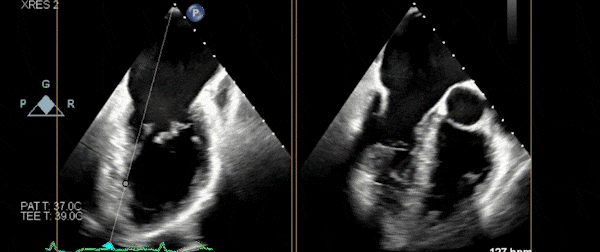

术前3D

手术过程

在超声指导下顺利穿刺房间隔,沿输送系统将NeoNova® C6夹合器送至左房,调整夹合器位置和orientation后进行跨瓣。经确认将C6送达3区,操作捕获瓣叶,确认前后瓣叶充分捕捉后夹闭C6。

图片

第一枚夹合器夹闭&解离

依据术前策略,将第二枚NeoNova® C6夹合器送至第一枚C6外侧,使两枚夹合器临近,夹闭第二枚C6后超声示两枚夹合器紧邻,组织桥稳定,跨瓣压差2mmHg;但外侧仍残余反流、脱垂,因此决定植入第三枚夹合器。